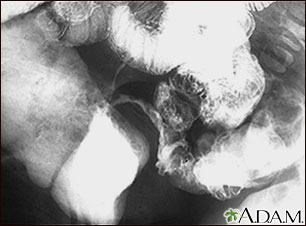

This lower abdominal x-ray shows narrowing (stenosis) of the end of the small intestine (ileum), caused by Crohn's disease. Crohn's disease typically affects the small intestine, whereas ulcerative colitis typically affects the large intestine. A solution containing a dye (barium), was swallowed by the patient. When it passed into the small intestines, this x-ray was taken (lower GI series).